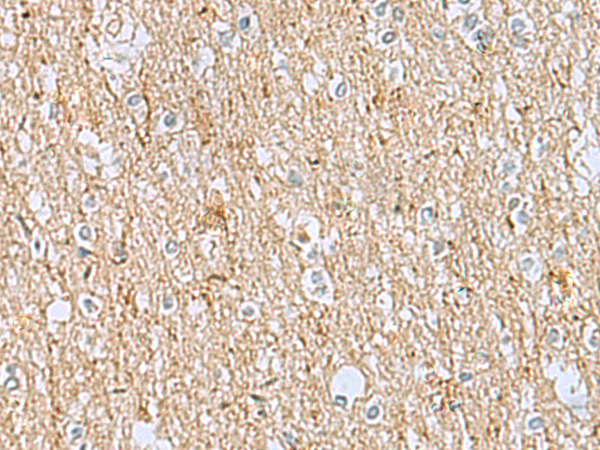

分类: 科研抗体货号: P12782别名: DEL5q14.3; C5DELq14.3应用: IHC反应种属: Human, Mouse